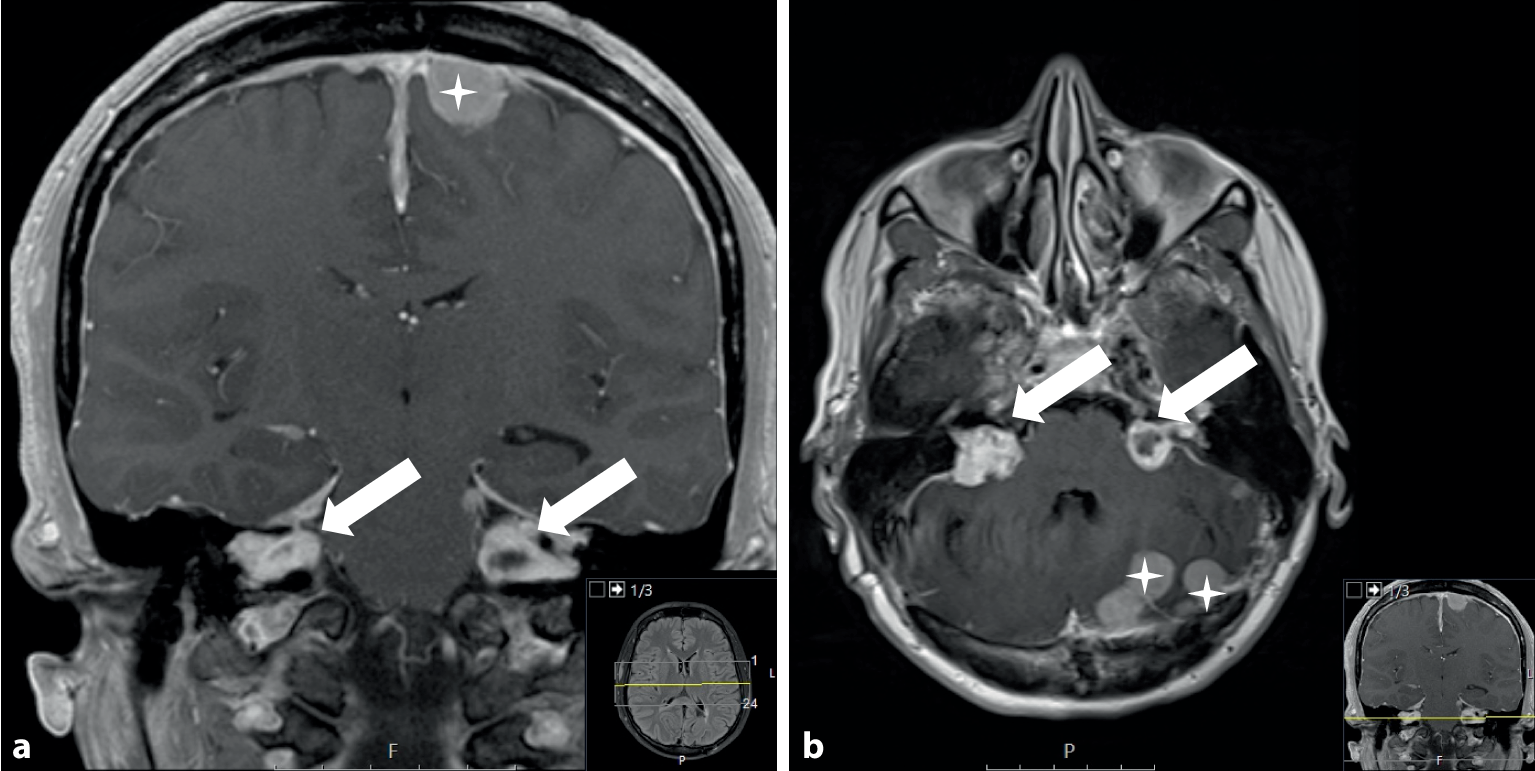

• Die NF2-bedingte Schwannomatose ist eine autosomal-dominant vererbbare Erkrankung, deren Hauptmerkmal die Bildung bilateraler Vestibularisschwannome (historisch: Akustikusneurinome) darstellt (Abb. 1; [2]).

Abb. 1

Vestibularisschwannome (VS) und Meningeome. Kontrastverstärkte 3 T-MRT (3T = 3 Tesla, Feldstärke des MRT) des Schädels einer 27-jährigen Patientin mit NF2; T1-Sequenz in koronarer (a) und transversaler (b) Schichtführung: bilaterale Vestibularisschwannome (Pfeile) sind das Kernkriterium der NF2-bedingten Schwannomatose. Aufgrund der häufigen Mosaikbildung bei der NF2 treten sie gelegentlich auch nur einseitig auf, im Vollbild der Erkrankung sind sie jedoch praktisch immer bilateral aufzufinden und führen in unterschiedlicher Ausprägung zu einer Hörminderung sowie zu Schwindelsymptomen; typischerweise zeigen Patienten mit trunkierenden Varianten im NF2-Gen einen wesentlich schwereren Verlauf (Wishart-Phänotyp), wohingegen Missensevarianten zum milderen Gardner-Phänotyp führen. Daneben finden sich bei vielen Patienten intrakraniale (Sterne) oder spinale Meningeome, nichtvestibuläre Schwannome anderer Hirnnerven, spinale Schwannome sowie Schwannome der peripheren Nerven. Spinale Ependymome treten typischerweise beim Wishart-Phänotyp auf